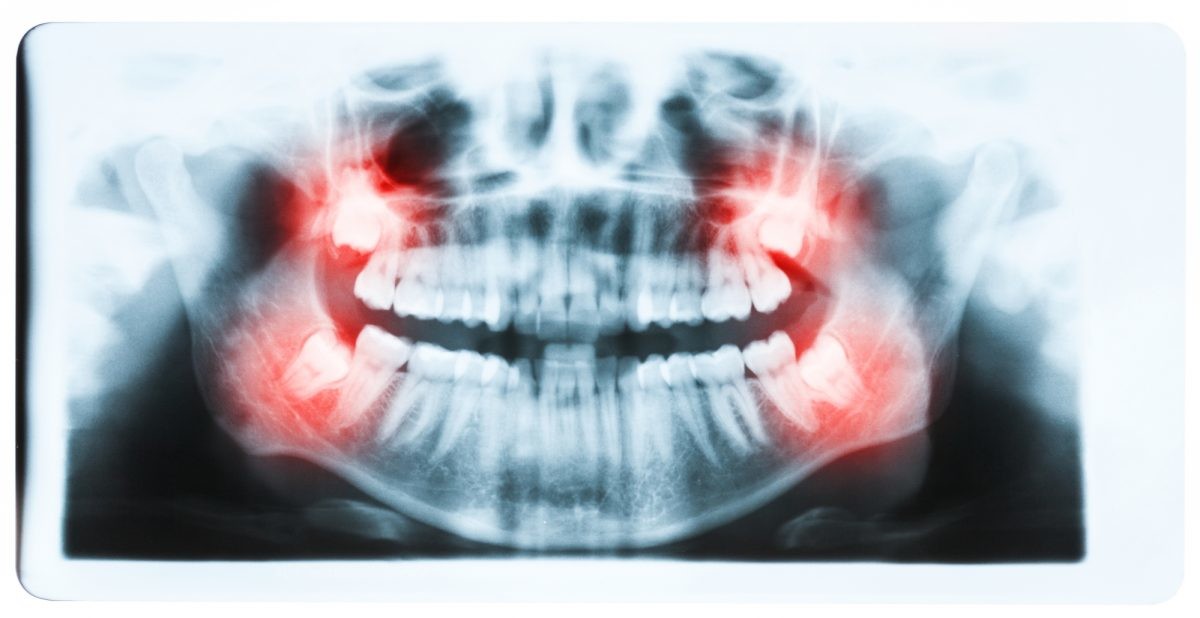

For those people who have wisdom teeth, they usually erupt in early adulthood. Wisdom teeth may cause dental issues like overcrowding, especially if they’re impacted. However, many people have plenty of room for their wisdom teeth and they have no problems with them.

During this age frame, many people also get braces or just have them removed. People are often concerned that the eruption of their wisdom teeth will affect the progress they’ve made with braces.

However, if they do not come in correctly or if a person’s jaw simply doesn’t have room for the new teeth, they can cause overcrowding among the back teeth.

While wisdom teeth may not necessarily cause a major issue with the dental progress that has been made with braces, there may still be reasons to have a wisdom tooth extraction. There are many wisdom tooth concerns that may call for tooth removal surgery, including: Crowding of back teeth, Infected gums, Bone defects, Root resorption, Dental diseases.

If a wisdom tooth becomes impacted or doesn’t erupt straight up, this can cause significant problems for the person. While some people may experience absolutely no problems with their wisdom teeth or get lucky enough to not have any of these extra molars at all, others may experience problems with them.

Fortunately, impacted tooth removal is a common procedure and can provide relief from any pain and discomfort caused by these teeth. In fact, wisdom teeth removal is more common than dental implant procedures, which about three million people have every year.

It’s important to remember that it’s perfectly normal for your teeth to move as you age. If your wisdom teeth are beginning to come in and are causing you pain and discomfort, your dentist may refer you to an experienced oral surgeon to discuss having them removed.